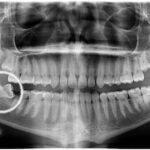

¿Cómo cuidar los dientes de sus hijos?

Consejos sobre higiene dental de los más pequeños de la casa